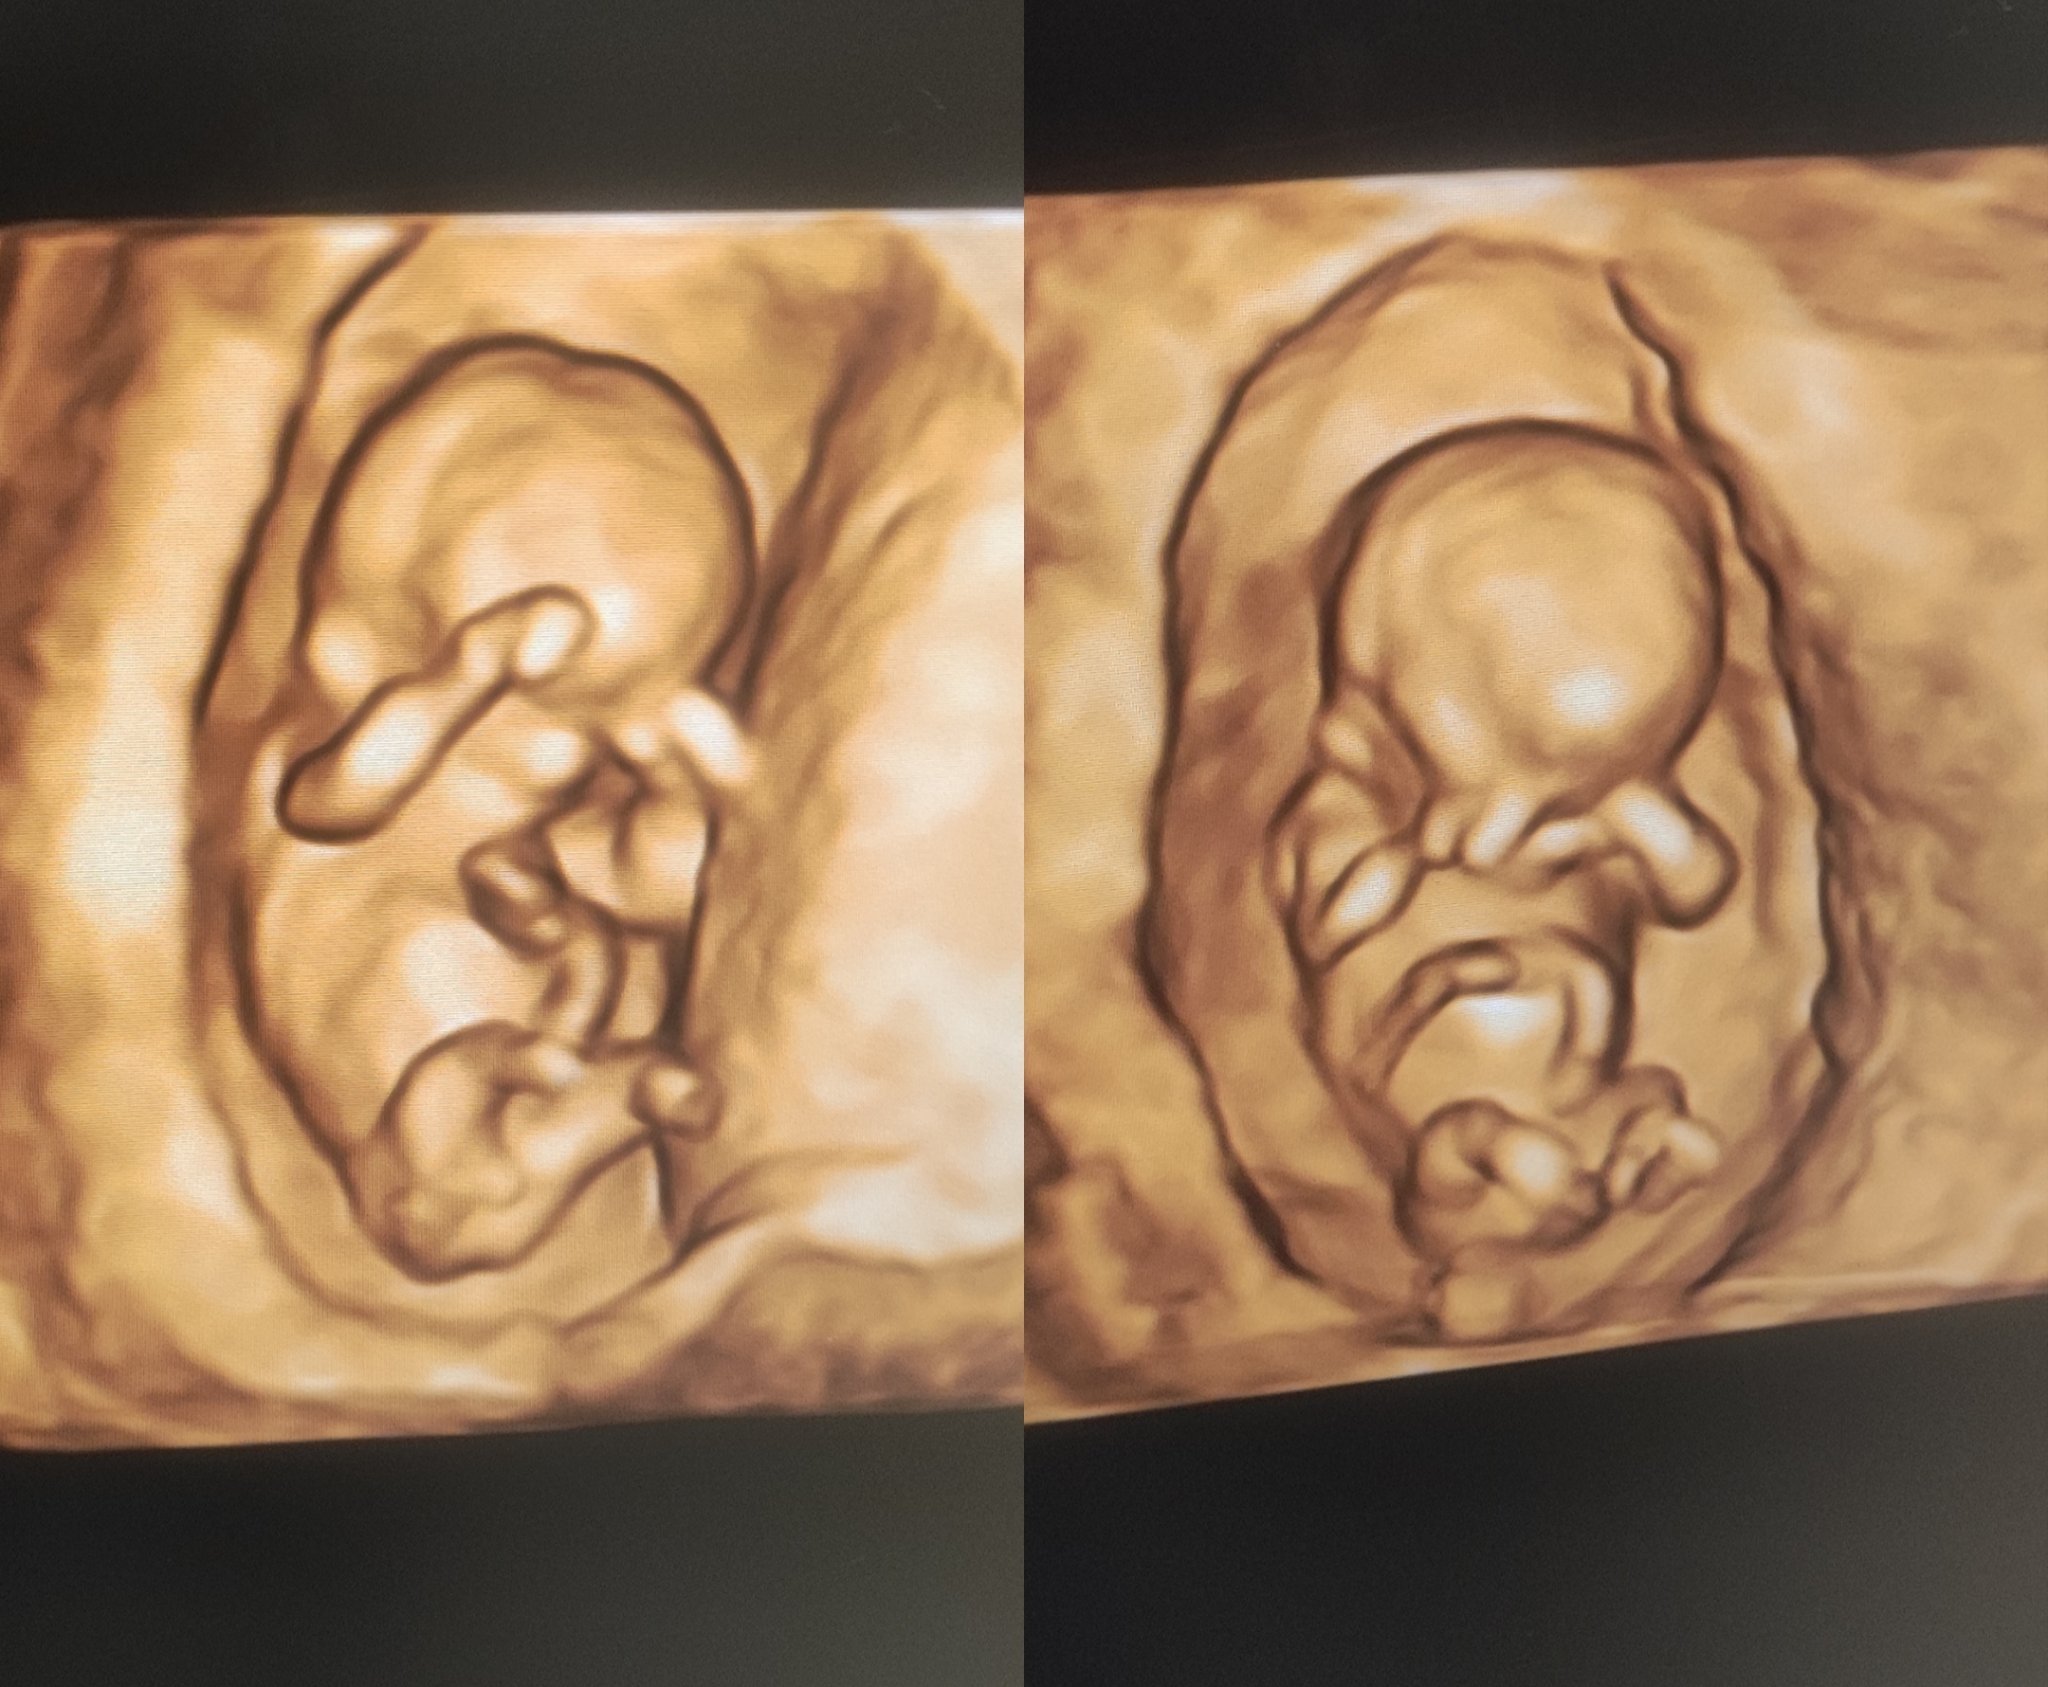

Здравейтеее! Първата фетална морфология мина❤️🙏🏽 Всичко е наред с бебенцето. АГ се опита да предположи за пола, каза първо момче - след това момиче 🫣😁 на вас на какво ви прилича??☺️☺️

Ох, как се е сгушило, като котенце 🥰 Аз мисля, че е момченце, ама съм далеч от експерт по определяне на пола. А че е сладичко спор няма. 🤍

Не е специално 3D / 4D изследване, а фетална морфология. И теб така ще те погледнат и на 4Д и 3Д🌷🥰

При мен за съвсем кратко включиха този 4D режим само колкото да го видя как изглежда реално в пространството. Иначе всичко важно си се гледаше по стандартния начин. Извадиха ми една такава и още 5-6 нормални снимки. И моето беше така с ръцете пред лицето – класическа поза Grinning